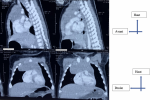

Démarche diagnostique: une tomodensitométrie thoracique avait par la suite été réalisée, ayant permis de mettre en évidence une masse médiastinale antérieure, de densité tissulaire, développée aux dépens du thymus, avec comme mensurations 56 mm x 52 mm de grand axe. Elle exerçait un effet de masse sur le parenchyme pulmonaire gauche et droit (Figure 3 et Figure 4).

Figure 3: tomodensitométrie thoracique: coupes transversales

Figure 4: tomodensitométrie thoracique: coupes sagittales et coronales